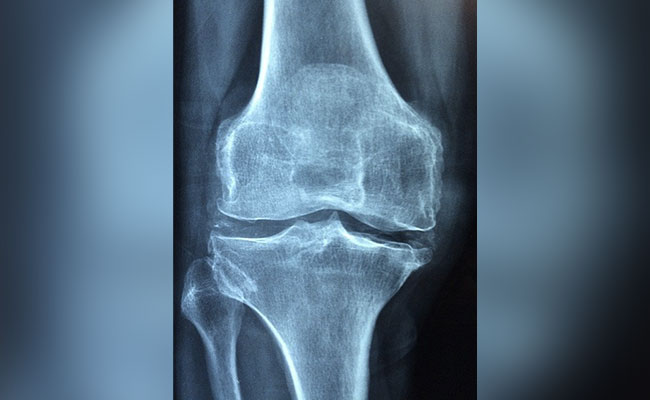

Facts About Bones And Joints: हड्डियां शरीर का बहुत जरूरी हिस्सा हैं. हड्डियां आपस में जुड़ी रहती हैं और बॉडी को आकार और सपोर्ट देती हैं. यह बॉडी के महत्वपूर्ण अंगों जैसे दिल को सुरक्षा देने का भी काम करती हैं. हड्डियों को मजबूत (Strong Bones) रखने के लिए कैल्शियम, फास्फोरस और प्रोटीन से भरपूर डाइट के साथ विटामिन डी (Vitamin D) की जरूरत होती है. इसके साथ ही नियमित एक्सरसाइज से हड्डियों की सेहत बेहतर रखने में मदद मिलती है. उम्र के साथ हड्डियां कमजोर होने लगती है और फ्रैक्चर का खतरा बढ़ जाता है. आइए जानते हैं हड्डियों और जोड़ों के बारे में कुछ मजेदार फैक्टस, जिसे शायद आप अब तक न जानते हों.

जोड़ के बारे में कुछ मजेदार फैक्ट्स (Fun Facts About Joints)

- दो हड्डियों के मिलने वाली जगह को जोड़ कहते हैं.

- हड्डियों को एक दूसरे से लिंगामेंट्स जोड़ते हैं. ये कठोर कनेक्टिव टीश्यू होते हैं और दो हडिडयों को जोड़कर, जोड़ या ज्वाइंट्स बनाते हैं.

- कार्टिलेज या उपास्थि नामक फाइब्रस (रेशेदार) टिश्यू हड्डी की ऊपरी सतह को ढक कर रखती है हड्डियों को एक-दूसरे के रगड़ खाने से बचाती हैं.

- कुछ जोड़ हिलते हैं और कुछ नहीं. खोपड़ी के जोड़ नहीं हिलते नहीं हैं जबकि सिनोवियल ज्वाइंट्स हिल सकते हैं. शरीर में अधिकांश जोड़ सिनोवियल ज्वाइंट्स होते हैं.

- घटने और कोहनी में हिंज ज्वाइंट होती है. यह दरवाजे के लगे हिंज की तरह काम करते हैं.